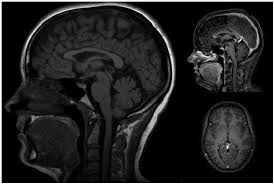

The diagnosis of pineal cyst is usually established by MRI with defined radiological criteria to distinguish benign pineal cyst from tumors of this area. A pineal cyst is usually only treated if it causes symptoms. In order to detect the presence of a cystic mass in the head magnetic resonance imaging is required.

Evaluation Of Pineal Cysts With Magnetic Resonance Imaging